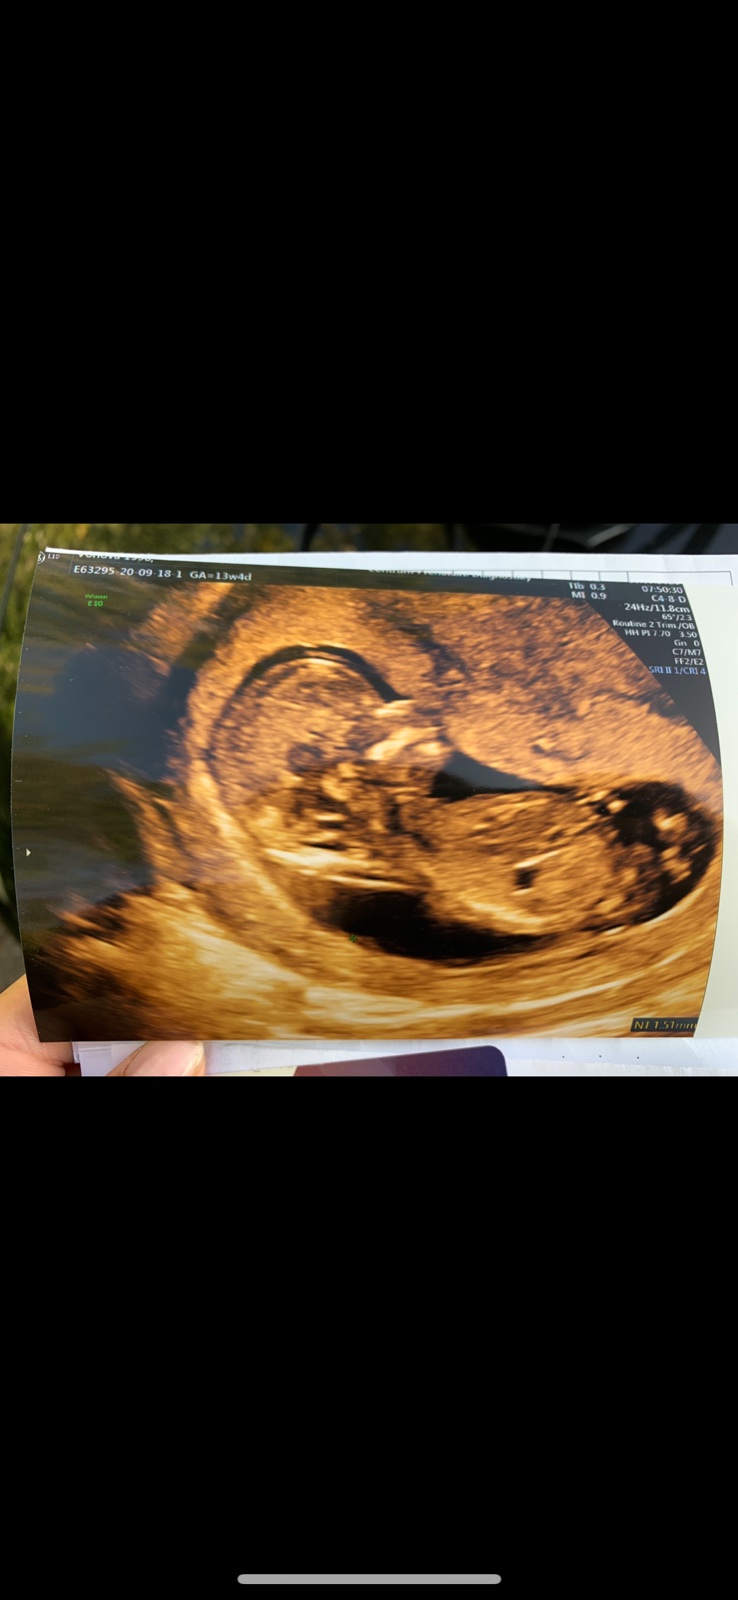

@pavlinkadv No jenže v tom 17. týdnu už není pohlavní hrbolek, ten je kolem 13. týdne

@rennye já mám fotku ze 13. tt 😉

Ze 17. tt dávala jiná nastávající maminka 😊

@pavlinkadv Aha, no i tak to jde špatně vidět, ale u Vás bych řekla spíše chlapeček, zdá se mi, že se tam něco stohuje nahoru 😉